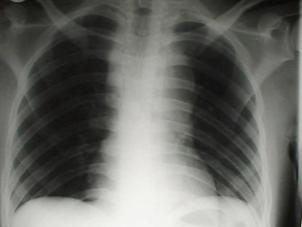

Pneumotorace sufocant bilateral Pneumotorace sufocant stang

Pneumotorace

sufocant stang Pneumotorace